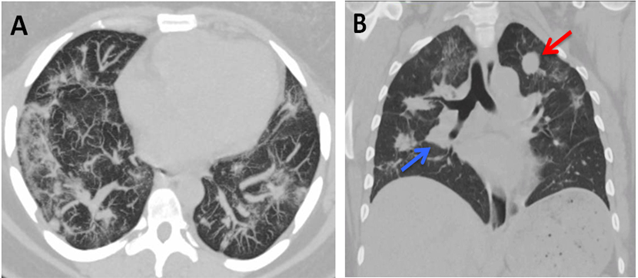

Laboratory workup showed a microcytic anemia, with hemoglobin of 9.2 gm/dL and mean corpuscular volume of 65.5 fL, which were within her normal baseline. Further, the cardiology team evaluated her, and studies from Zio Patch cardiac monitoring, stress test and echocardiogram were all unremarkable. She was started on Carvedilol 6.25mg twice a day for her uncontrolled hypertension. Pulmonary function testing demonstrated severe restrictive physiology with total lung capacity (TLC) 35% of predicted, forced expiratory volume in one second (FEV1) 34% of predicted, forced vital capacity (FVC) 31% of predicted and no response to bronchodilators. Patient was unable to perform testing for diffusion capacity of the lungs for carbon monoxide. A subsequent computed tomography (CT) scan of her chest showed multiple nodular opacities throughout both lungs, including the left lung apex and right perihilar region Figure 1.

Figure-1. CT of the chest without contrast. A) Diffuse patchy opacities in both lungs. B) Well-circumscribed masslike soft tissue nodule in the left lung apex (red arrow) and a masslike opacity in the right perihilar region (blue arrow).